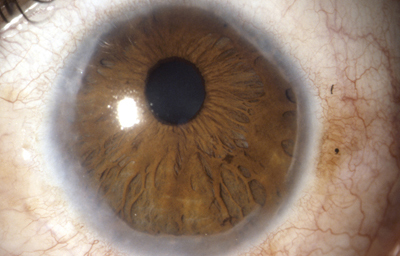

Anomalias del Estroma: Hiperplasia, Hipoplasia

Hiperplasia

Archivo fotográfico Dr. Francisco Barraquer.